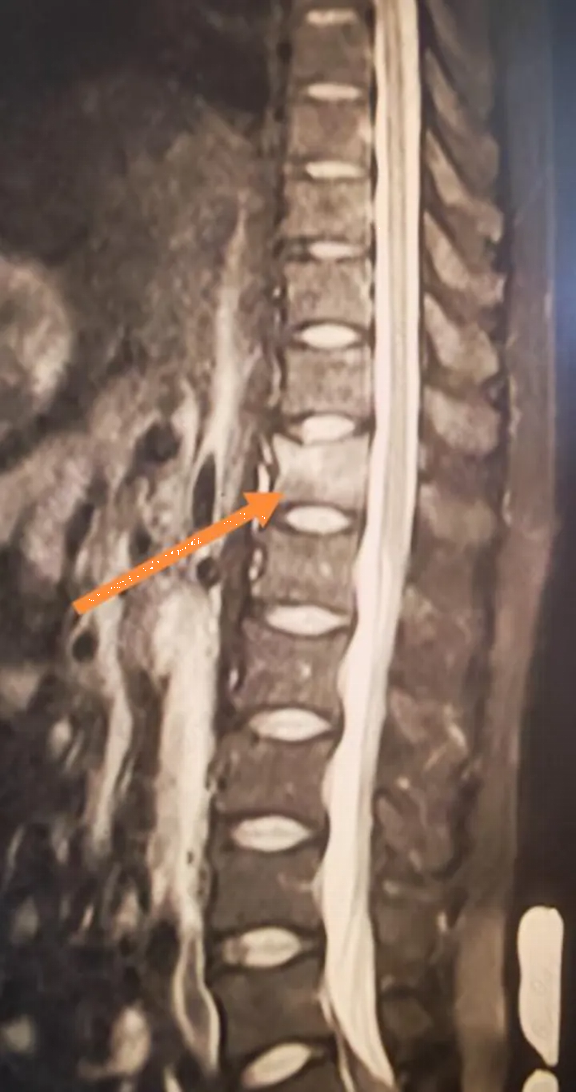

Kết quả chụp MRI khiến anh hoàn toàn sững sờ: gãy xẹp đốt sống T12.

Người đàn ông 34 tuổi xương giòn như bà cụ 60 tuổi vì ngày nào cũng uống 3 cốc loại nước nhiều người không thể sống thiếu - Ảnh 1.

Các xét nghiệm tiếp theo cho thấy kết quả còn gây sốc hơn chỉ số Z-score L1-L4 của anh Lý chỉ là -3,1, nghĩa là mật độ xương của anh thấp hơn so với hầu hết phụ nữ 60 tuổi. Một loạt các xét nghiệm đã loại trừ khả năng loãng xương thứ phát. Kết quả xét nghiệm cho thấy nồng độ vitamin D của anh Lý chỉ ở mức 10 ng/ml, thấp hơn nhiều so với tiêu chuẩn bình thường.